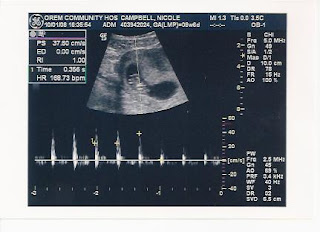

So this whole thing was never really honestly real to me before today. I mean sure, I had some morning sickness, dizziness and am always tired. But that didn't mean a whole lot until today. At my appointment I met one of the midwives and she was really great. She taught me a lot and asked me a ton of questions. I didn't get a full head to toe exam since I am only 9 weeks. I have another appointment on my 12 week day to get the full "detail". However she heard me say that I wanted a ultrasound so desperately today. So she said she would tell the hospital that we were not sure the due date so we needed to do an ultrasound to get a better idea. :) I measured nine weeks as of today, Wednesday. And my due date is now May 7th!

Seeing the baby and then hearing the heartbeat was by far one of the most amazing moments in my life thus far. I know that may sound stupid, but I have yet to stop smiling since we left the hospital. Thinking this is something that would never in a million years happen to us makes this even more of a miracle. Today started out really horrible, selling my wedding ring for way under price to pay bills was awful. I cried a lot, just because it was something that meant a lot to me. But it was cured for the time being seeing our little sticky bean on the screen! So here are some more of the pictures we got from him, one of them shows the heartbeat at 168.73 per minute, which he said was perfect! YAY